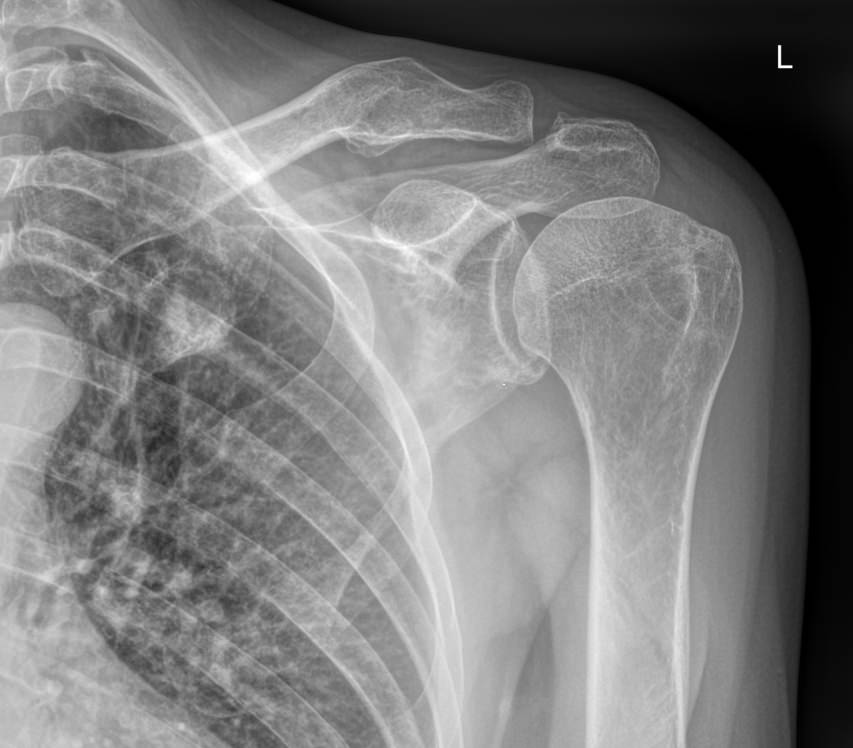

Рентгенография относится к стандартным методам диагностики плечевых суставов. На снимке можно обнаружить все патологические изменения, произошедшие в данной области, а также стадии болезни. Рентген используется также для выбора метода лечения и его контроля. Рентгеновское оборудование последнего поколения позволяет делать серию снимков с минимальной дозой облучения. Это важно, так как дает возможность выполнить необходимое количество снимков в динамике.

Снимки выполняются в разных проекциях, в зависимости от того, какой элемент сустава требуется визуализировать.

• Костно-травматические изменения ― переломы, вывихи, остеофиты;

• Состояние суставных поверхностей ― не нарушено, эрозии;

• Суставные щели ― сужение, обызвествление капсулы, наличие выпота;

• Изменения в костных тканях ― изменений нет или наблюдаются разные патологии;

• Изменения в мягких тканях ― отечность, инородные тела;

• Новообразования любой природы.